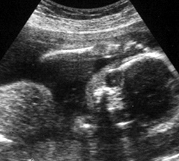

Baby Philipsen at 24 weeks

However, baby had other ideas. We clearly saw 10 fingers, 10 toes, 2 legs, healthy heart and spine, a head….a very healthy and very squiggly fetus. However, baby became very shy at the moment of gender discovery…even the doc said “Don’t pick out your paint colors yet.”